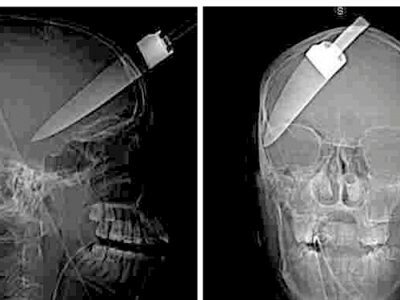

2dor Posted August 11, 2009 Posted August 11, 2009 Nu este fictiune, ci o scena sinistra, vazuta pe viu in Bucuresti. In rolul principal a fost distribuit un tanar de 23 de ani, internat de altfel la urgenta. Un sofer l-a dus in mare graba la doctor. De parca scena pe care a vazut-o conducatorul auto nu ar fi fost suficient de halucinanta in sine, comportamentul victimei i-a dat fiori. Barbatul mergea cu cutitul infipt in cap, extrem de linistit, de parca nimic nu s-ar fi intamplat. Misterul avea sa fie spulberat la camera de garda a spitalului Floreasca. Analizele, obligatorii inainte de operatie, au demonstrat ca victima agresiunii era indopata cu heroina. De aceea nici nu a putut spune ofiterilor, inainte sa intre in blocul operator, cine, unde si de ce l-a atacat cu un cutit de bucatarie. Pana sa intre in operatie, anestezistii au avut ceva bataie de cap, sa refaca dozajul de anestezic, pentru ca tanarul drogat cu heroina putea sa nu fie sedat de o doza normala. Medicii au descoperit ca respectivul cutit ii fusese infipt intre tampla stanga si mandibula, cam prin dreptul urechii. Lama de 12 centimetri a trecut razant pe langa cutia craniana. Asa se face ca nici un centru al creierului nu a fost atins. Operatia a decurs cu bine, lama a fost scoasa din capul tanarului si cel mai probabil acesta nu va ramane cu sechele neurologice. Acum, politia trebuie sa descalceasca toata povestea. Sursa: ProTV.ro Link: aici Me: Ma intreb de ce nu folosim stupefiante pe post de anestezic Medicii au reusit sa-l salveze si chiar i-au scos cutitul din cap tanarului de 23 de ani care marti mergea pierdut si plin de sange prin Bucuresti. Link2: acilea

Stalk3r Posted August 11, 2009 Posted August 11, 2009 interesant , dar radiografia aia nu prea pusca una cu alta..

LuckyShot Posted August 11, 2009 Posted August 11, 2009 pozele nu sunt de la articol. pe site nu e decat video si acolo arata clar cum a fost de fapt cutitul infipt si anume perpendicular pe tampla. macar aveti si voi curiozitatea si uitati-va

2dor Posted August 13, 2009 Author Posted August 13, 2009 Nu prea seamana a2a imagine cu prima pozele nu sunt de la articol. pe site nu e decat video si acolo arata clar cum a fost de fapt cutitul infipt si anume perpendicular pe tampla. macar aveti si voi curiozitatea si uitati-va nu au avut timp sa developeze radiografiile